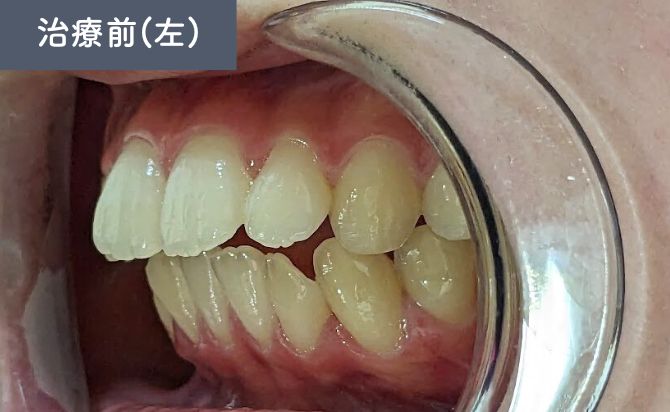

歯並びの変化(左)